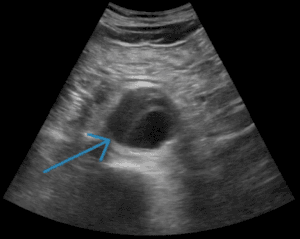

It is estimated that 50% of deaths due to abdominal aortic aneurysms (AAA) could be prevented by a national screening program [1, 2, 3]. Thanks to technological ad­vancements and cost reductions, point-of-care ultrasound (POCUS) in family medicine (FM) is becoming more prev­alent [4, 5]. Despite the potential utility of POCUS in FM, of 224 FM residency programs surveyed, only 21% had developed a curriculum [6]. The main barriers identified to establishing a FM POCUS curriculum in Canadian FM residency programs were lack of trained faculty, lack of adequate equipment and lack of time in the curriculum [6].

Our study tested a pilot POCUS curriculum for first year FM residents which was developed to improve competency in screening for AAA using POCUS. To address the barrier of many learners, and few trained faculty, we incorporated a “train-the-trainer” model. The first set of two residents were trained by Canadian POCUS (CPOCUS)-certified faculty mem­bers [7] during a week of evening clinics. These two resi­dents subsequently trained the next subset of two resi­dents, tumbling forward over four weeks until eight resi­dents were trained. This minimized direct faculty teaching time.

During both OSCEs, the CPOCUS-certified examiner directly observed residents measure the aorta and assessed them using an established rubric in order to assess competence. However, one limitation is that the quantitative accuracy of the actual AAA measurements performed by the learner during training was not directly assessed by the instructor. This could have been achieved by comparing the trainee’s measurements with a CPOCUS-certified trainer’s findings on the same abdominal aorta. Accuracy is important because: 1) false negative measurements would mean that prevention of a life-threatening condition (AAA=related mortality, rupture and emergency repair) could have been avoided, and 2) false positive measurements generate unnecessary con­firmatory imaging, follow-up care including emergency transfer and specialist referrals, and undue patient stress. Blois (2012) did demonstrate that a family physician could develop an accuracy with less than 0.2 mm discrepancy from official measurements but the physician in this study received significantly more training (i.e. 50 supervised scans) [1].